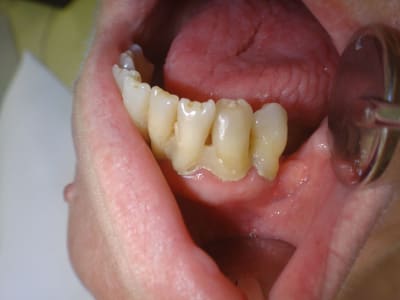

Ici une 37, complètement asymptomatique après un "soin" remontant à 5 ans...

Image extraite d'une pano.